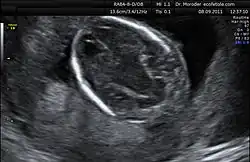

Nicolaides besuchte während seiner Schulzeit The English School in Nikosia, studierte Medizin am King’s College School of Medicine and Dentistry in London und trat 1980 der Abteilung für Gynäkologie und Geburtshilfe unter Stuart Campell und Charles Rodeck bei. Dort betrieb er Forschungen zur Fetoskopie. Nach dem Weggang von Charles Rodeck wurde er Direktor des Harris Birthright Research Centre for Fetal Medicine[2], der ersten Abteilung für Fetalmedizin im Vereinigten Königreich. Er entwickelte die Technik der Chordozentese weiter und veröffentlichte als erster eine wissenschaftliche Veröffentlichung zum Thema der endoskopischen Lasertherapie bei fetofetalen Transfusionssyndrom.[2] Er veröffentlichte auch zahlreiche Papiere zum Thema Ultraschall in der Pränatalmedizin, so beschrieb er als erster das lemon-sign und das banana-sign welches bei Spina bifida auftritt und er untersuchte systematisch die Nackentransparenz. Insgesamt veröffentlichte er über 500 Artikel sowie 30 Bücher und Monographien.[2] Sein h-Index beträgt 177 und ist damit im Bereich der Frauenheilkunde und Gynäkologie der weltweit höchste.[3]